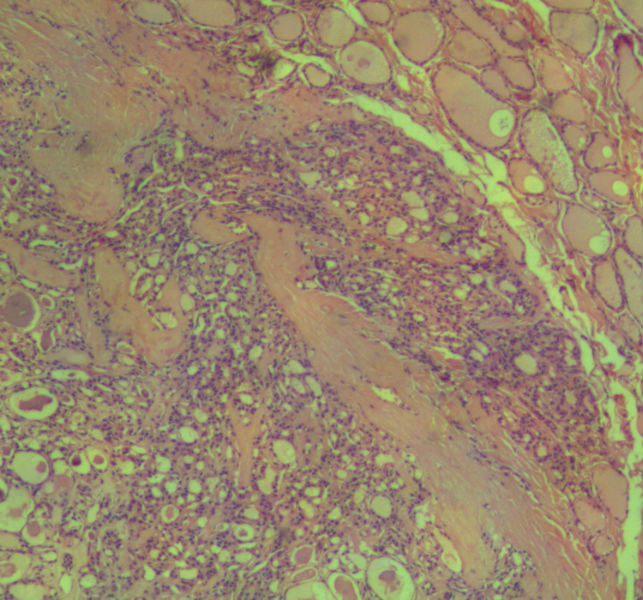

女,45岁,体检发现颈前区一结节,术中送检甲状腺左腺叶,发现一界清结小1*0.8cm,灰黄色。术中诊断滤泡性肿瘤伴包膜累及,局部疑包膜穿破,滤泡癌可能,待石蜡报告。石蜡连续切片形态见图,可见明显包膜穿破,诊断为滤泡性癌。患者借片到上级医院会诊,结果为:包膜内滤泡癌伴包膜累及。请问有包膜内滤泡癌的提法吗?这个病例怎么诊断啊?请各位老师多指导。

• 这个是滤泡性癌吗图2

图2

甲状腺滤泡癌确实分2型:浸润型包膜不完整,明显浸润周围甲状腺组织;包裹性血管浸润型有包膜,但有血管或包膜浸润。

本例包膜不完整,应该是滤泡癌。